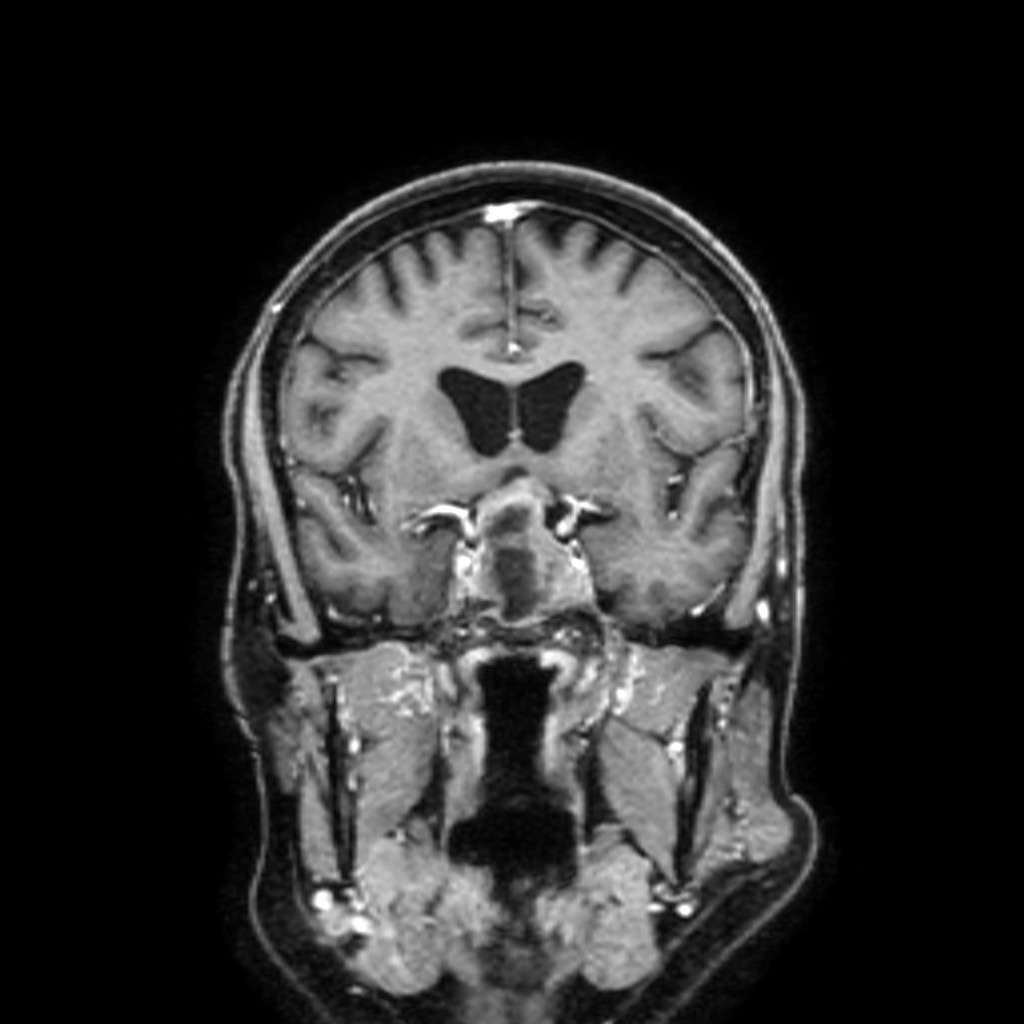

Adenoma ipofisario su RM

L’adenoma ipofisario è abbastanza frequente però, per fortuna, è molto spesso asintomatico. In caso di scoperta occasionale, è consigliato seguire l’evoluzione radiologica con delle risonanze magnetiche annuali.

Se l’adenoma ipofisario è più grande, può provocare due problemi principali. Il primo problema è uno squilibrio ormonale causato da una importante produzione di un ormone dal tumore stesso. In questo caso i sintomi sono aspecifici, come la presa o perdita di peso, il diabete oppure un problema tiroideo. Il secondo problema, specifico per un adenoma ipofisario, è la perdita di una parte del campo visivo dovuto alla compressione delle vie ottiche da parte del tumore.